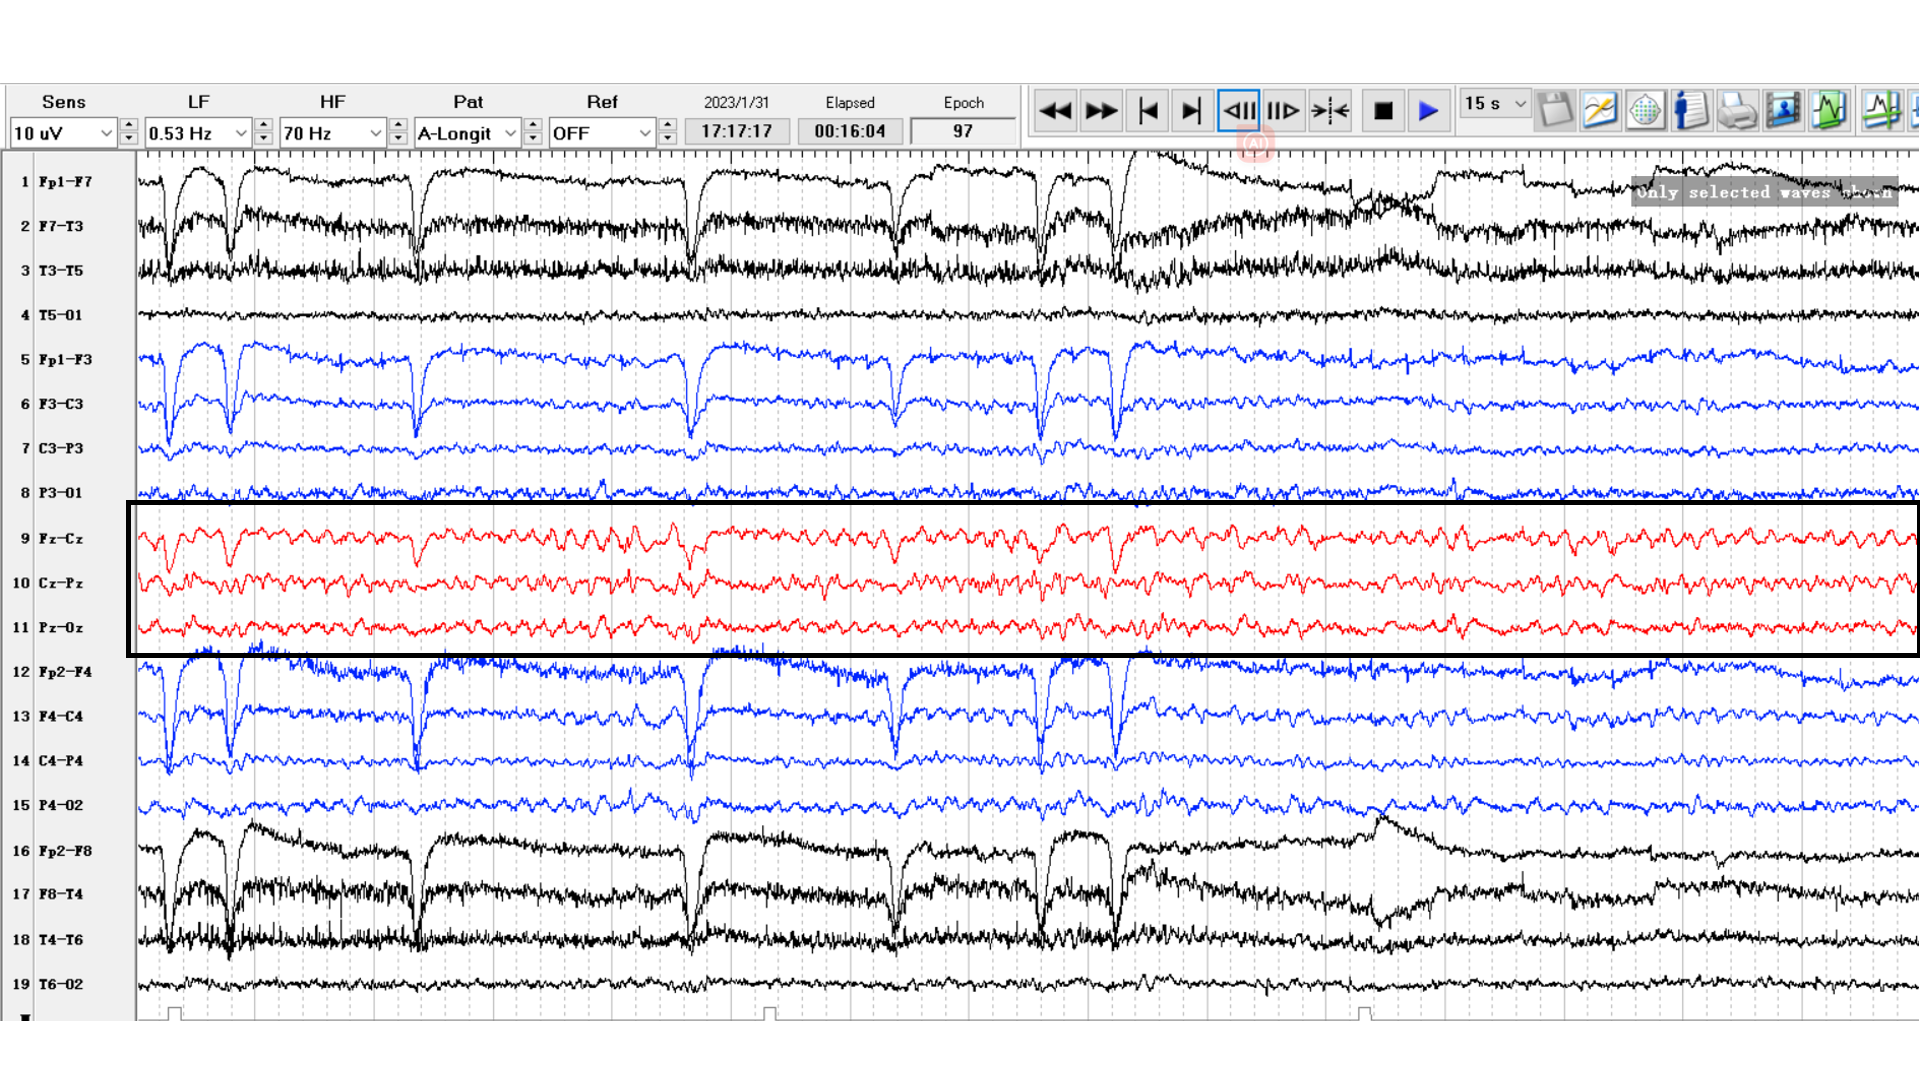

头皮电极脑电图可见中线区近持续性癫痫放电。发作期可记录到左上肢肌阵挛-失张力发作(图2,图3)。

图2 头皮脑电图示中线区近持续性癫痫放电(黑色方框)